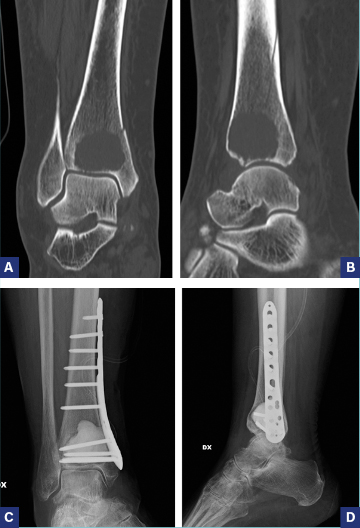

La stabilizzazione preventiva o su frattura mediante intervento di infibulo endomidollare deve sempre osteosintetizzare (o stabilizzare) l’intero segemento ed è riservata a pz con scarsa prognosi in cui permette un rapido sollievo dal dolore e ripresa della funzionalità (Fig. 2).

Deve essere associata sempre a radioterapia post-operatoria. Le localizzazioni metafisarie possono essere controllate meglio con intervento di curettage e placca dopo riempimento con cemento (Fig.3 a-d). La cementoplastica è emersa come una promettente opzione clinica, sicura e fattibile soprattutto per le sedi più complesse come l’acetabolo26.